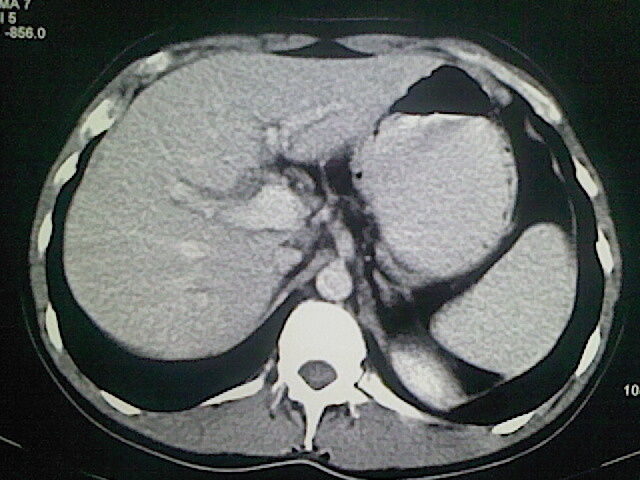

以下是引用卜一在2009-3-14 9:49:00的发言:[br]胆囊萎缩,胆囊壁不规则增厚,内部结构模糊,增强明显强化。另:肝左叶外侧段肝囊肿。支持:慢性胆囊炎!高度可疑:胆囊癌!

以下是引用余辉在2009-3-14 8:48:00的发言:[br]1)慢性胆囊炎。2)肝左叶外侧段肝囊肿。3)脂肪肝。[br]支持,胆囊萎缩,密度增高,不知b超具体有何提示,钙胆汁?结石?

以下是引用jiangjing在2009-3-14 10:18:00的发言:[br]1)慢性胆囊炎。2)肝左叶外侧段肝囊肿。3)脂肪肝。4.】建议行肝功能检查